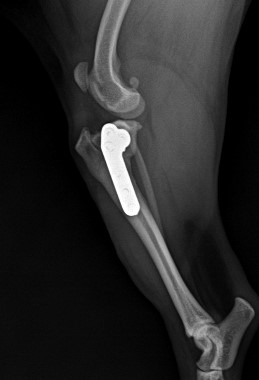

체중을 전혀 싣지 못하고 드는 상태)가 관찰되었습니다. 엑스레이 검사에서도 아래쪽 경골이 앞쪽으로 밀리는 drawer sign이 명확히 확인되었습니다.

수술 후 엑스레이 사진 / 출처: 미래동물의료센터

수술 후 비교적 빠른 시기부터 보행이 점차 안정적으로 회복되는 모습을 보였으며, 통증 조절과 회복 반응도 양호한 편이었습니다.